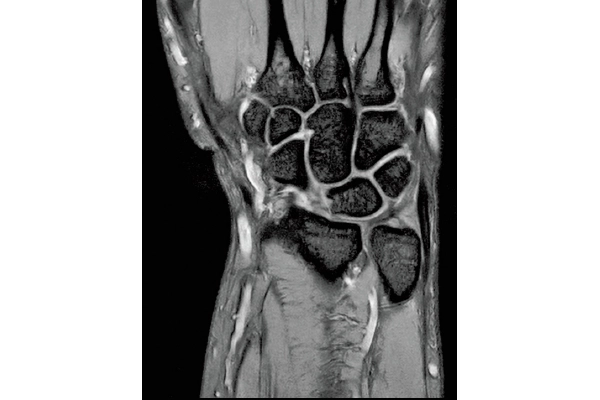

T2*WI Multi Echo,

0.38×0.38×2.0mm

0.35×0.40×3.0mm, 2:55

3D Bone

0.93×0.93×1.2(0.6)mm

1.1×1.1×1.2(0.6)mm

3DisoFSE T2WI

0.75×0.75×1.1(0.55)mm

MPR COR